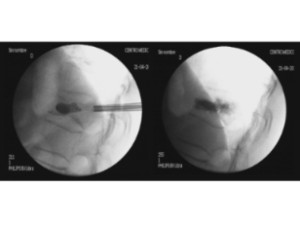

Estabilización percutánea de fracturas vertebrales inestables

En casos de fracturas vertebrales complejas, inestables, conminutas, etc. se requiere una estabilización adicional de la fractura mediante una artrodesis percutánea, y en algunos casos en los que hay compromiso neurológico, una descompresión del canal medular. La artrodesis percutánea permite estabilizar la estrctura comprometida de la columna vertebral y descargar la carga del paciente sobre la fractura. Adicionalmente se suelen cementar las vertebras artrodesas y la fractura vertebral mediante cifoplastia.

Caso clínico con estabilización percutánea de fractura vertebral inestable.